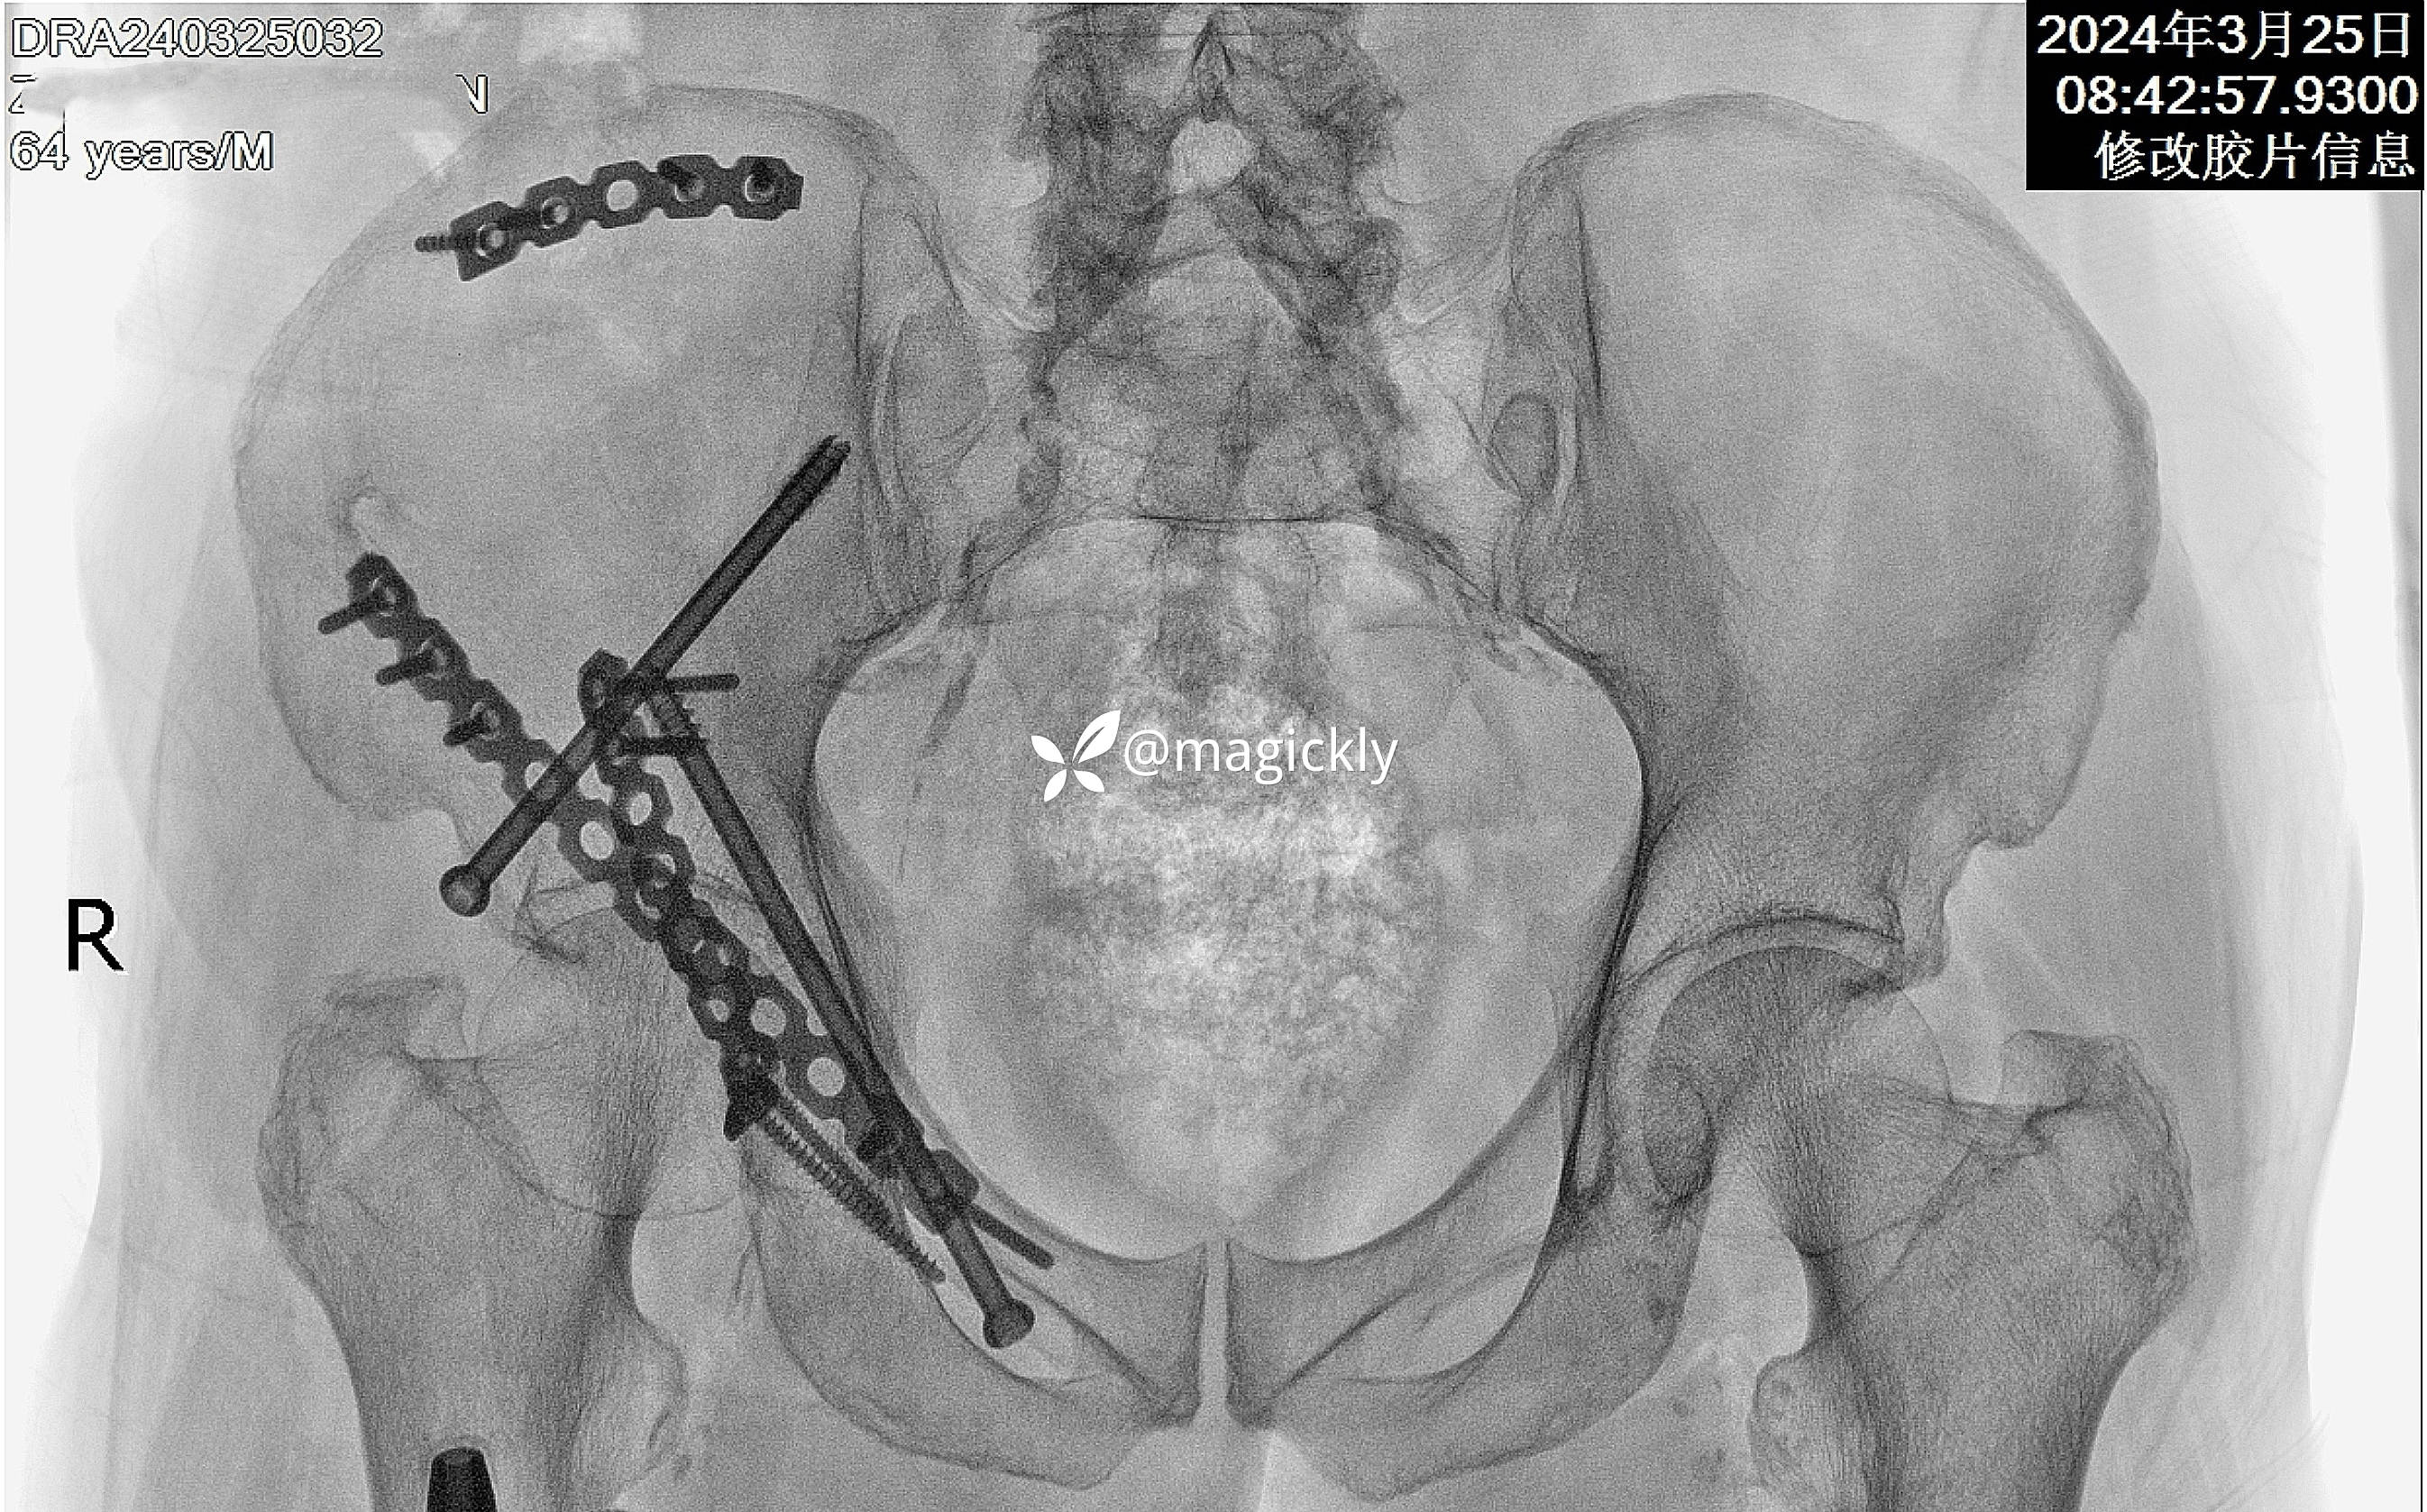

【治疗经过及结果】